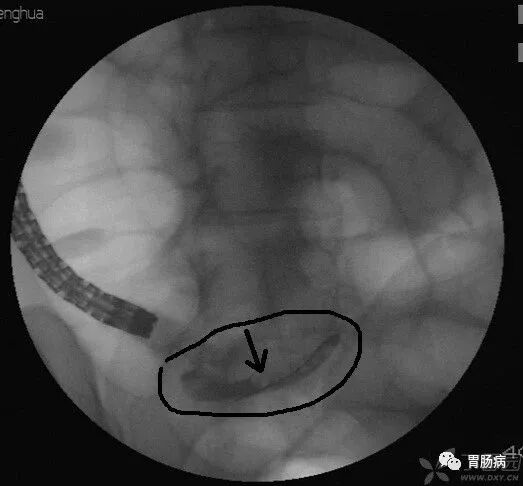

X线下,阑尾腔内注入造影剂显示阑尾腔的形态(椭圆形线圈),如有粪石(黑箭头),则行球囊取石术。并确认有无阑尾穿孔。